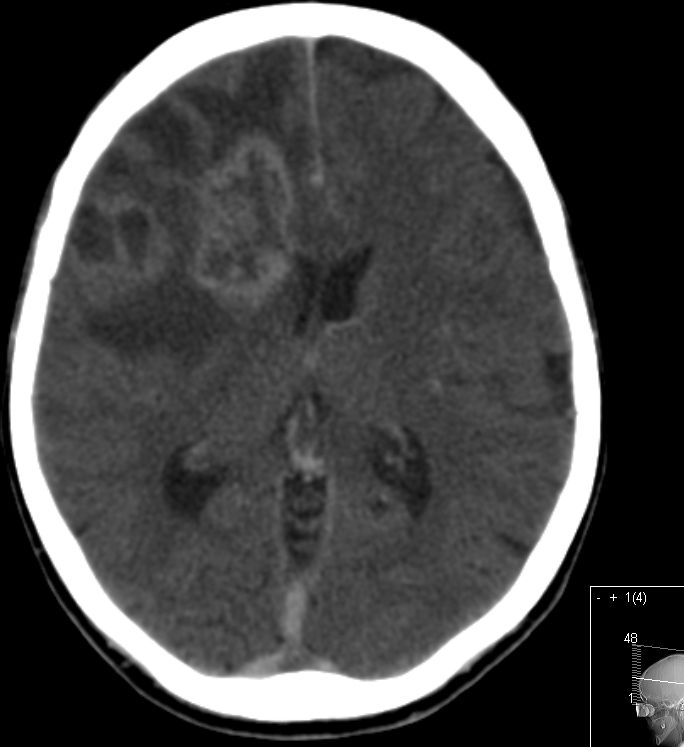

CT |

64-jährige Frau mir generalisierten Krampfanfällen und Hemiparese links.![]() | ||||